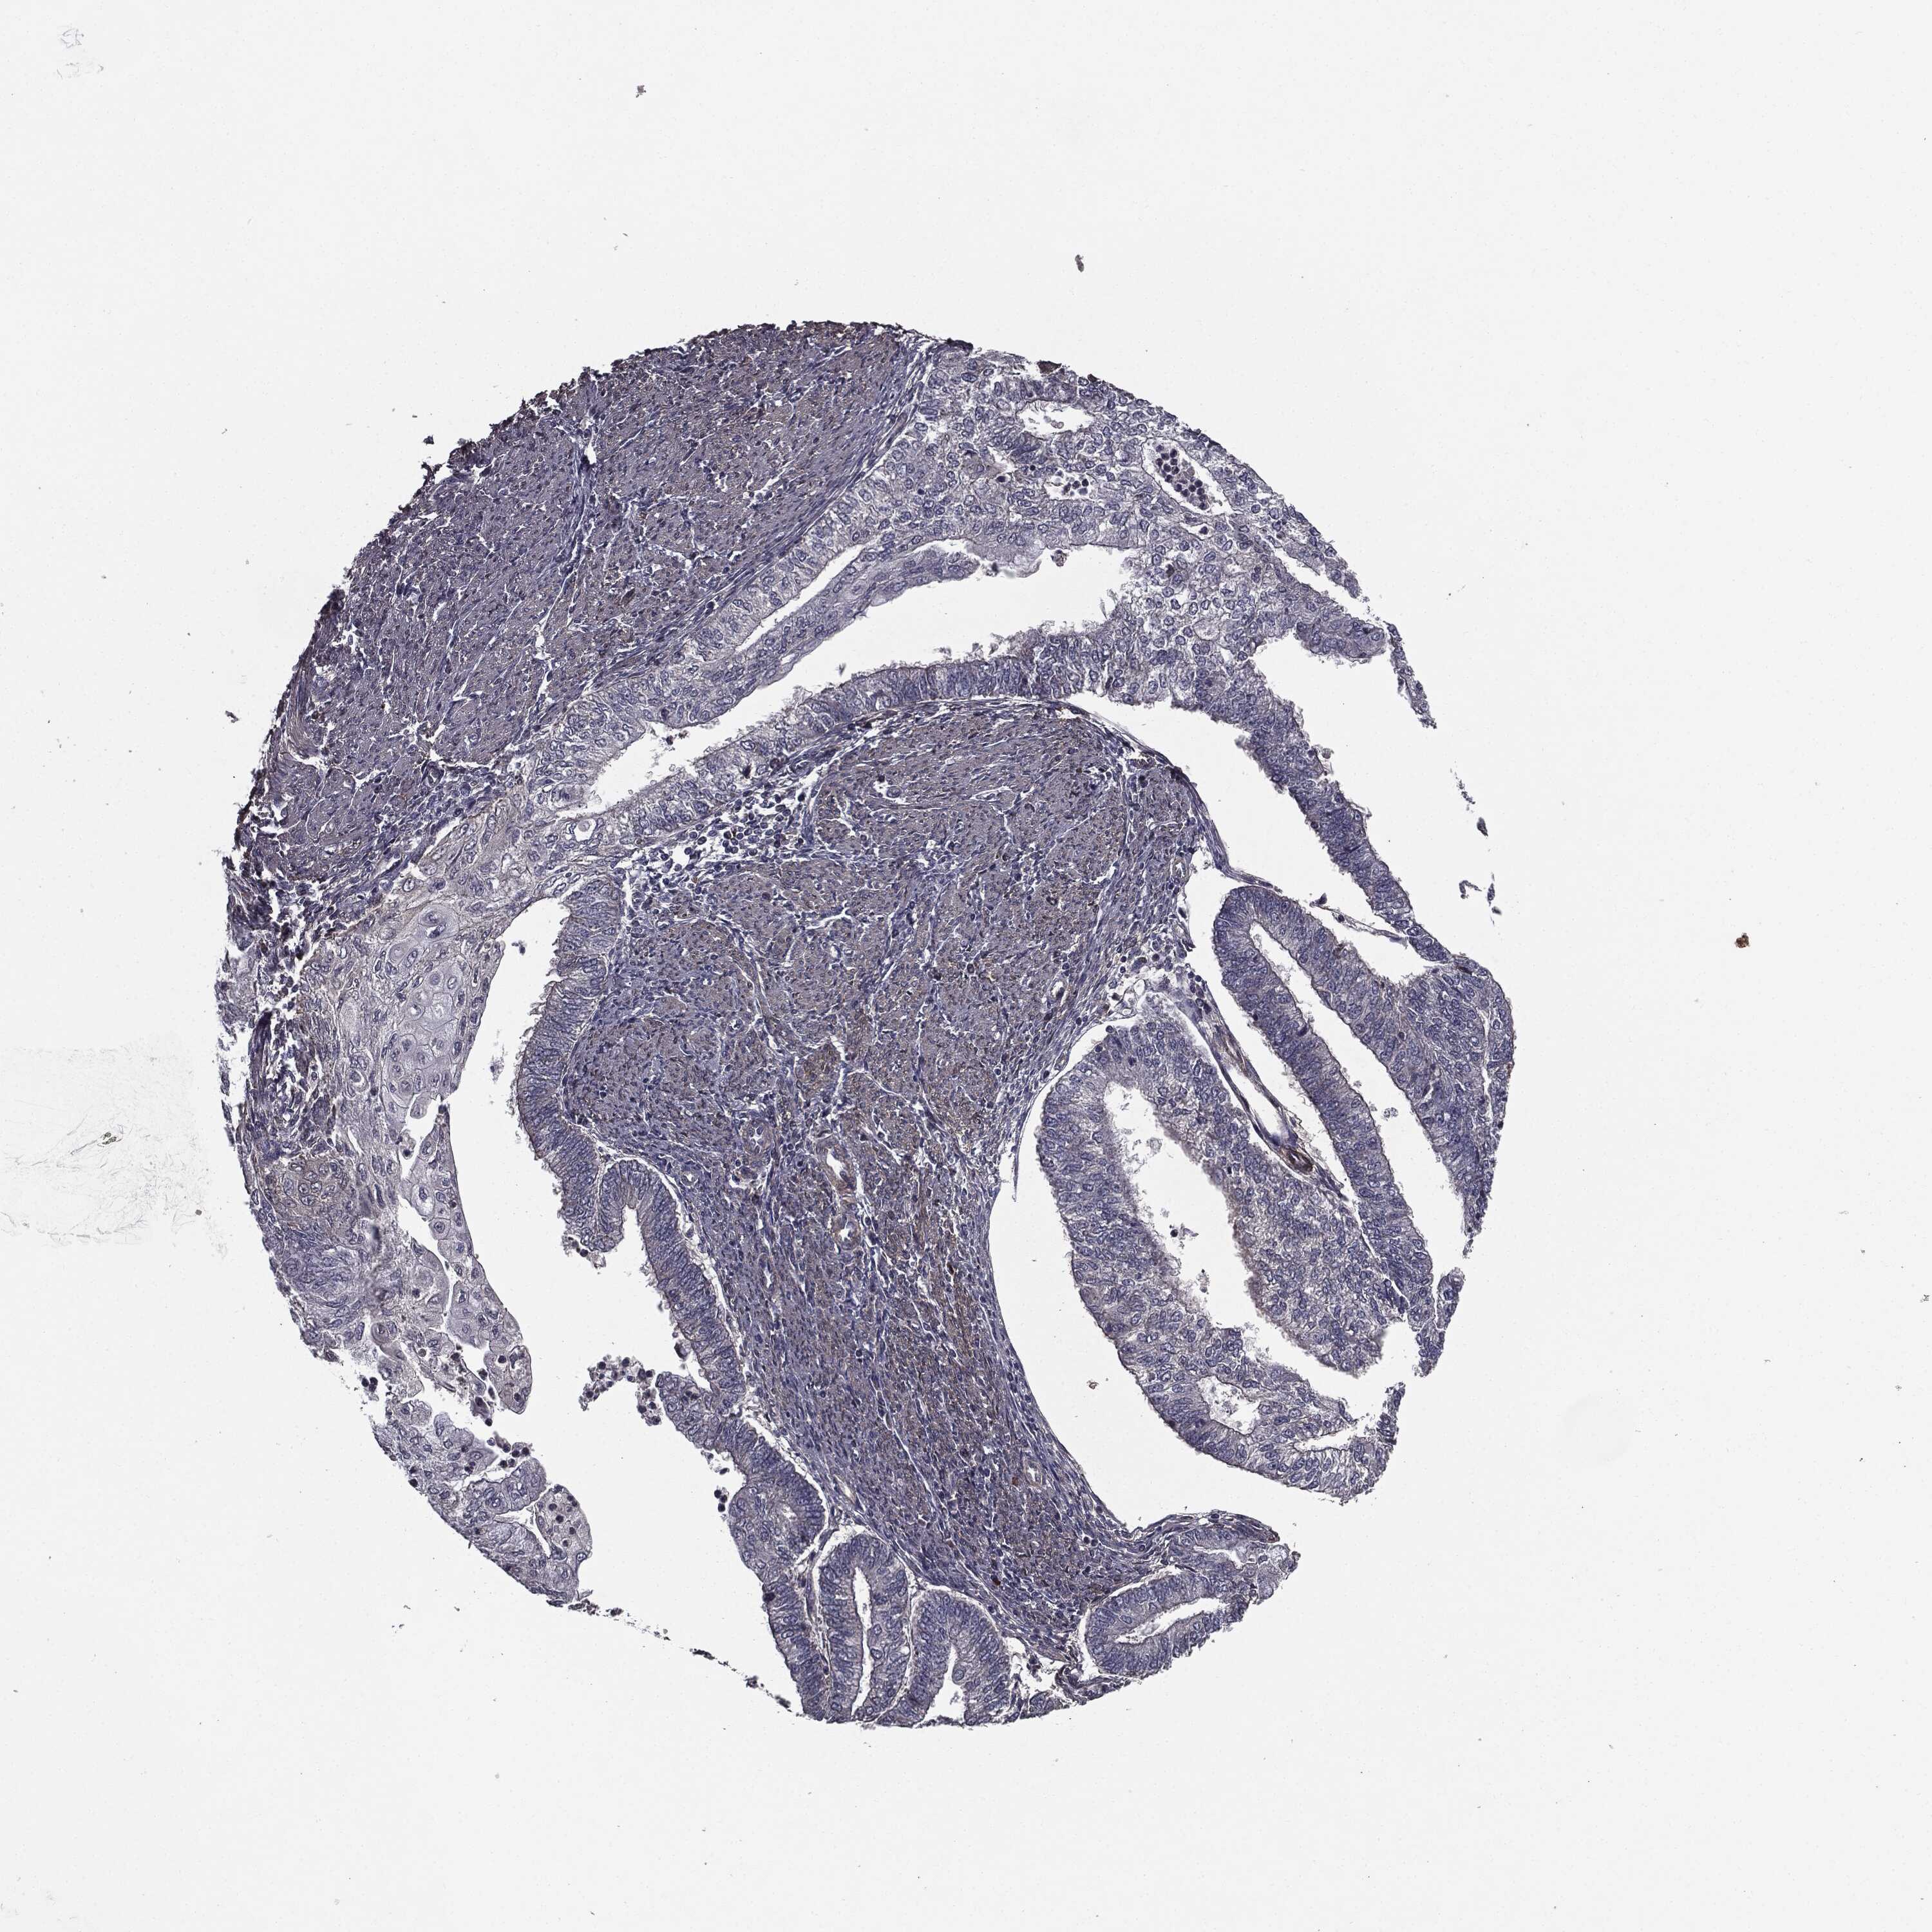

ENDOMETRIAL CANCER - Protein expressioni

A mouse-over function shows sample information and annotation data. Click on an image to view it in a full screen mode. Samples can be filtered based on level of antibody staining by selecting one or several of the following categories: high, medium, low and not detected. The assay and annotation is described here.

Note that samples used for immunohistochemistry by the Human Protein Atlas do not correspond to samples in the TCGA dataset.

Antibody stainingi

Antibody staining in the annotated cell types in the current human tissue is reported as not detected, low, medium, or high, based on conventional immunohistochemistry profiling in selected tissues. This score is based on the combination of the staining intensity and fraction of stained cells.

Each image is clickable and will lead to virtual microscopy that enables deeper exploration of all samples and also displays staining intensity scores, fraction scores and subcellular localization as well as patient and tissue information for each sample.

Antibody HPA052606

Antibody HPA077139

Staining

High

Medium

Low

Not detected

Intensity

Strong

Moderate

Weak

Negative

Quantity

>75%

75%-25%

<25%

None

Location

Nuclear

Cytoplasmic/membranous

Cytoplasmic/membranous,nuclear

Adenocarcinoma, NOS